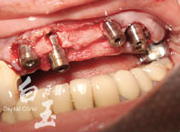

治療過程

植入植體